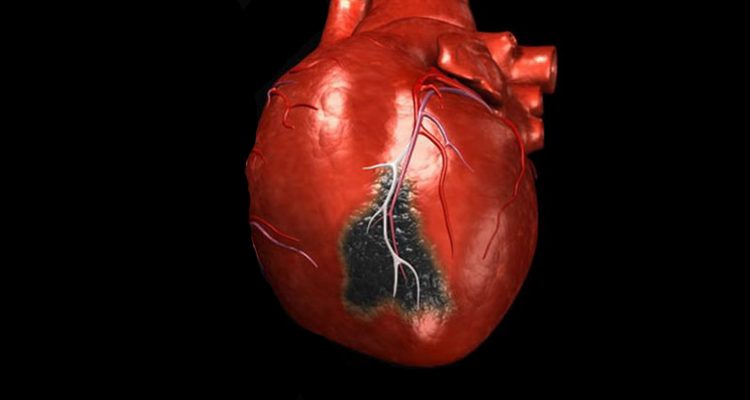

Серцевий напад відбувається, коли артерія, що постачає серце кров’ю і киснем, блокується тромбом. Найбільш частою першопричиною його утворення є ішемічна хвороба серця. Під час цього стану коронарні артерії забиваються відкладеннями холестерину, які і блокують кровотік.